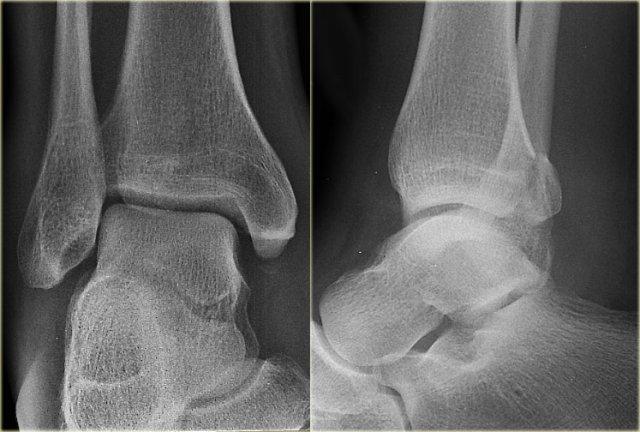

- Nhận định ban đầu

Có gãy xương mắt cá sau.

Không thể phân loại theo Weber.

Gãy xương mắt cá sau đơn độc là không phổ biến, nhưng khi là một phần của chấn thương sấp-xoay ngoài (Weber B) hoặc ngửa-xoay ngoài (Weber C) thì khá thường gặp.

Do đó, chúng ta cần xem lại phim để tìm kiếm các dấu hiệu của gãy xương Weber B hoặc C.

- Đánh giá lại

Không có dấu hiệu gãy xương chéo ở mắt cá ngoài, do đó có thể loại trừ gãy xương Weber B.

Vẫn còn khả năng gãy xương Weber C, bao gồm: đứt hoặc bong gân phía trong, gãy xương mác cao và cuối cùng là gãy xương mắt cá sau.

Lúc này chúng ta chú ý thấy hình ảnh bong gân nhỏ tinh tế ở mắt cá trong (mũi tên đỏ).

Phim X-quang bổ sung của chi dưới cho thấy gãy xương mác cao (mũi tên xanh). - Kết luận cuối cùng

Gãy xương Weber C giai đoạn 4.